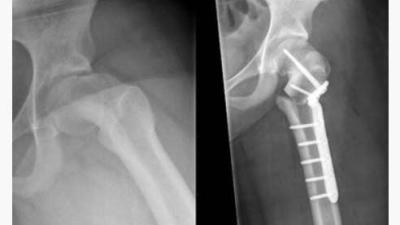

Voor het eerst in Nederland is een 3D-geprinte plaat gebruikt om een ‘afgegleden heupkop’ te corrigeren. Orthopedisch chirurg Melinda Witbreuk van OLVG

Om zich nog beter op een moeilijke operatie van botbreuken te kunnen voorbereiden hebben traumachirurgen van het Elisabeth-TweeSteden Ziekenhuis (ETZ) in